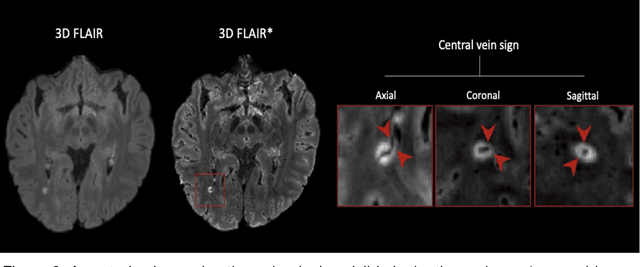

Abstract:The current multiple sclerosis (MS) diagnostic criteria lack specificity, and this may lead to misdiagnosis, which remains an issue in present-day clinical practice. In addition, conventional biomarkers only moderately correlate with MS disease progression. Recently, advanced MS lesional imaging biomarkers such as cortical lesions (CL), the central vein sign (CVS), and paramagnetic rim lesions (PRL), visible in specialized magnetic resonance imaging (MRI) sequences, have shown higher specificity in differential diagnosis. Moreover, studies have shown that CL and PRL are potential prognostic biomarkers, the former correlating with cognitive impairments and the latter with early disability progression. As machine learning-based methods have achieved extraordinary performance in the assessment of conventional imaging biomarkers, such as white matter lesion segmentation, several automated or semi-automated methods have been proposed for CL, CVS, and PRL as well. In the present review, we first introduce these advanced MS imaging biomarkers and their imaging methods. Subsequently, we describe the corresponding machine learning-based methods that were used to tackle these clinical questions, putting them into context with respect to the challenges they are still facing, including non-standardized MRI protocols, limited datasets, and moderate inter-rater variability. We conclude by presenting the current limitations that prevent their broader deployment and suggesting future research directions.